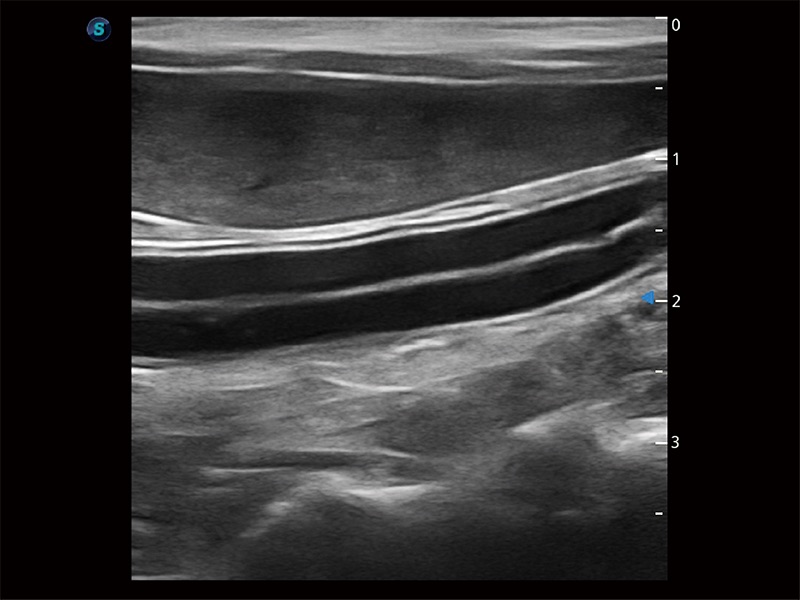

极大提升超低速微细血流的检出能力,同时更精准地滤除软组织和超声信号,为兽用医生提供以往无法通过常规血流获得的疾病诊断信息。